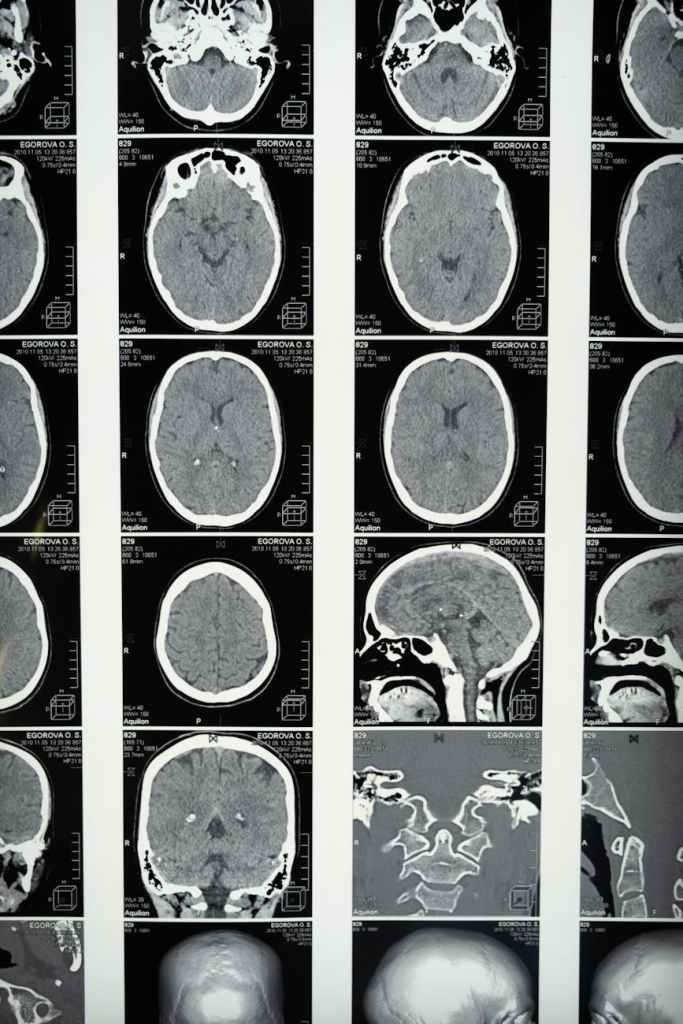

Brain disorders & other General topics of the day

This site aims to cover all sorts of brain conditions, mental health & some general everyday topics